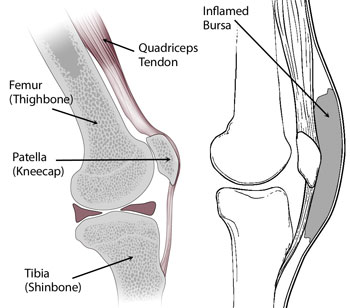

Супрапателлярный импиджмент коленного сустава: симптомы и лечение